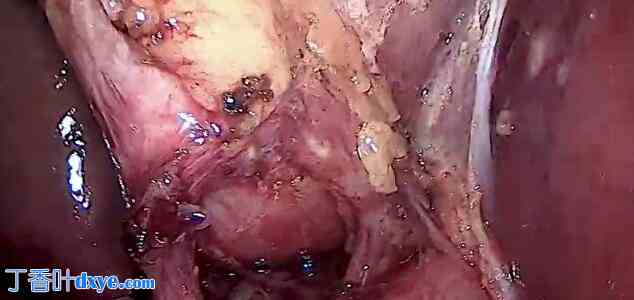

在胆囊板内进行解剖以形成肝囊窗

沿胆囊壁进行解剖以确保安全

安全性的关键术野

现在胆囊仅与胆囊管相连

将夹子应用于管道

导管向右倾斜可确保其胆囊管

从肝床分离胆囊